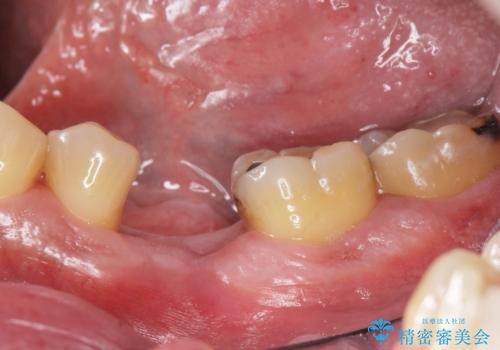

インレー下に再発した虫歯 セラミッククラウンによるやり替え